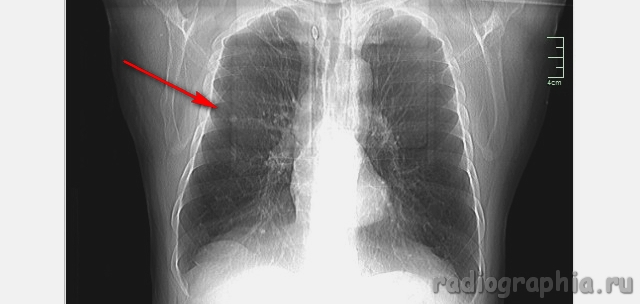

Одиночный узел правого лёгкого.

На рутинном снимке ОГК, был выявлен одиночный узел; по протоколу выполнили КТ. Какое было бы ваше заключение; и как бы Вы поступили если у вас нет возможности выполнять КТ?

Routine Chest X-Ray. SPN (solitary pulmonary nodule-red arrow)